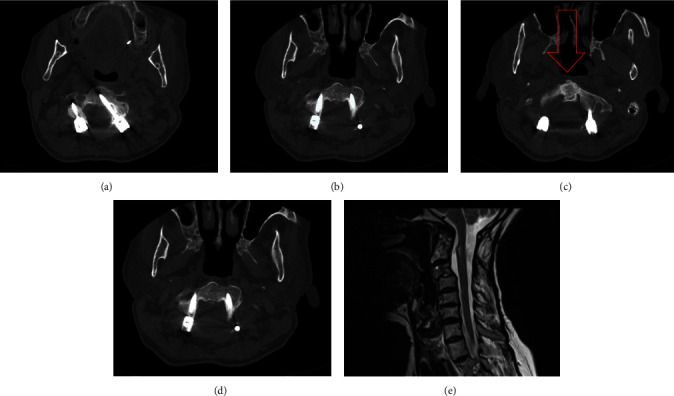

Background: Odontoid fracture (OF) is one of the most common spinal fractures. Type II in D'Alonzo's classification is still the most common and should be considered unstable unless proven otherwise. Thus, surgical stabilization has received significant attention. Although posterior displacement is common in type II OF, complete displacement is extremely rare, and very few reports are available in the literature. Case Presentation: We report the case of a 60-year-old man with acute type II OF with complete posterior displacement and myelopathy. The patient was managed utilizing a posterior-only single approach for reduction and stabilization. Conclusion: Posterior displacement of type II OF has been traditionally managed with close reduction and anterior or posterior stabilization. Closed reduction in cases of complete posterior displacement carries a significant risk of neurologic deterioration. Anterior, combined, and posterior approaches have been taken for this condition. The posterior-only approach in experienced hands has the least mortality and morbidity with at least the same neurologic and fusion outcomes.

Abstract Image